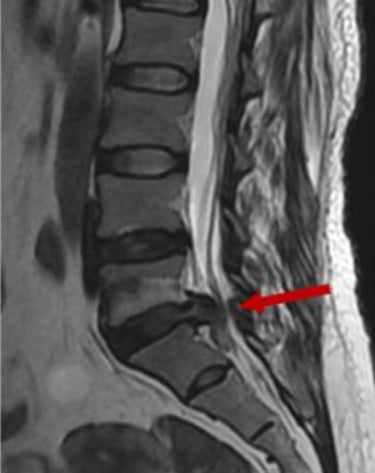

Tipo de hernia: las hernias extruidas o secuestradas (cuando el material se ha desplazado fuera del disco) tienen mayor probabilidad de reabsorción, ya que el sistema inmune puede acceder más fácilmente a ese tejido.

En cambio, las protrusiones discales (cuando el disco solo se abomba sin romperse) tienden a ser más estables y menos propensas a reabsorberse, aunque también pueden mejorar clínicamente con tratamiento conservador. El siguiente dibujo muestra la probabilidad de reabsorción según el tamaño de la hernia.